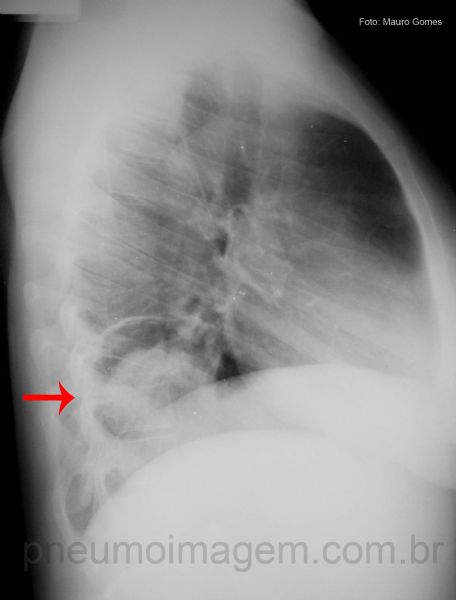

Nesta radiografia observa-se uma opacidade heterogênea e irregular localizada na região inferior do pulmão direito (seta). A formação em semilua (ou crescente) pode confundir com aspergiloma.

O corte em perfil localiza a lesão posteriormente. O sequestro é uma lesão que se encontra contígua ao pulmão normal, podendo ou não ser recoberto por pleura visceral.